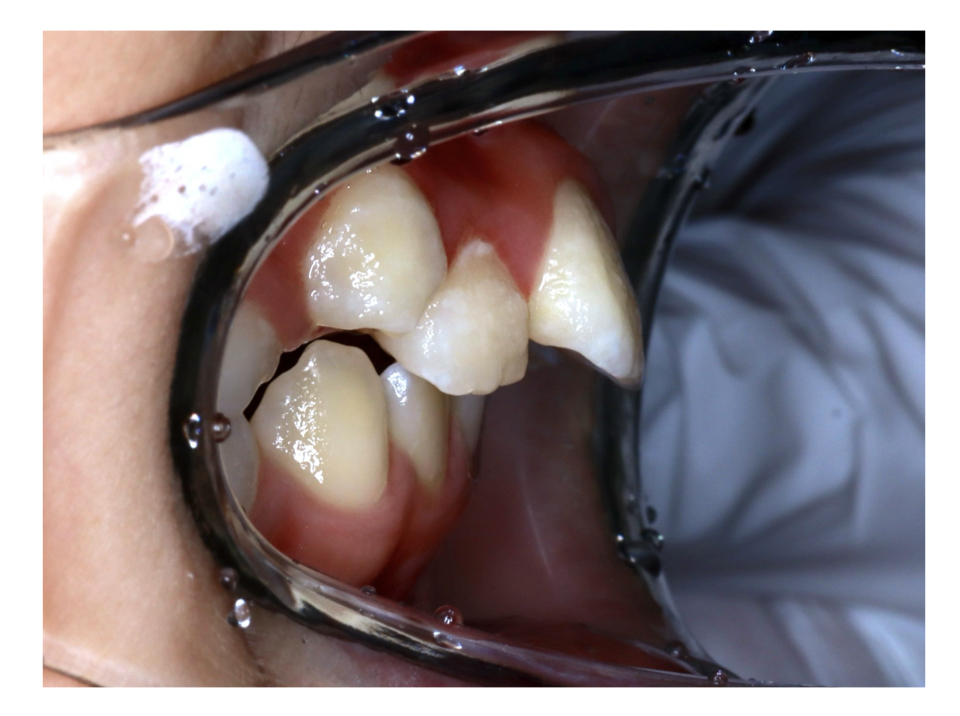

Case1

Before

After